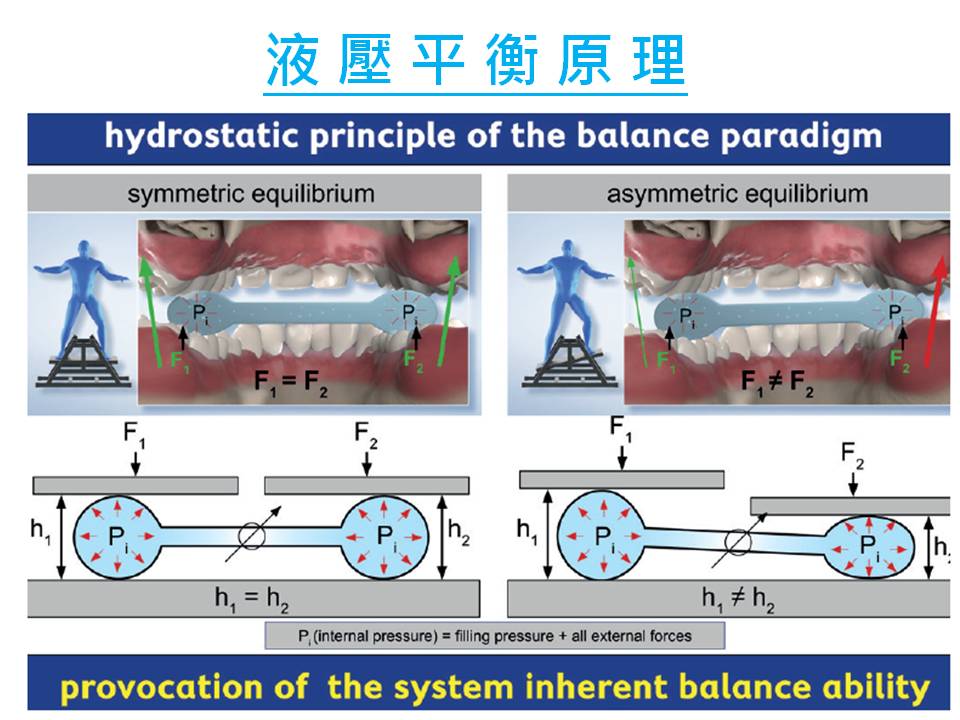

利用帕斯卡定律(Pascal’s Law),這個定律是指密閉容器中的靜止流體的某一部分發生的壓力變化,會毫無損失地傳遞至流體的各個部分與容器壁。。

換句話說,在水平衡咬合板上咬下去會導致使咬合力均勻分佈在整個咬合處的液體,減少了TMJ承受壓力和痛苦並確保緩解並使身體自然平衡,從而減輕TMJ疼痛并改進的功能。

換句話說,在水平衡咬合板上咬下去會導致使咬合力均勻分佈在整個咬合處的液體,減少了TMJ承受壓力和痛苦並確保緩解並使身體自然平衡,從而減輕TMJ疼痛并改進的功能。

水平衡咬合板的原理

水平衡咬合板是自然的基本物理定律的一種應用

稱為帕斯卡定律(Pascal’s Law),該定律規定將使用封閉流體

均衡的流體壓力,無論在何處施加壓力

流體。換句話說,在水平衡咬合板上咬下去會導致

使咬合力均勻分佈在整個咬合處的液體,減少了

TMJ承受壓力和痛苦並確保緩解並使身體自然平衡,從而減輕TMJ疼痛并改進的功能。

水平衡咬合板的原理

水平衡咬合板是自然的基本物理定律的一種應用

稱為帕斯卡定律(Pascal’s Law),該定律規定將使用封閉流體

均衡的流體壓力,無論在何處施加壓力

流體。換句話說,在水平衡咬合板上咬下去會導致

使咬合力均勻分佈在整個咬合處的液體,減少了

TMJ承受壓力和痛苦並確保緩解並使身體自然平衡,從而減輕TMJ疼痛并改進的功能。